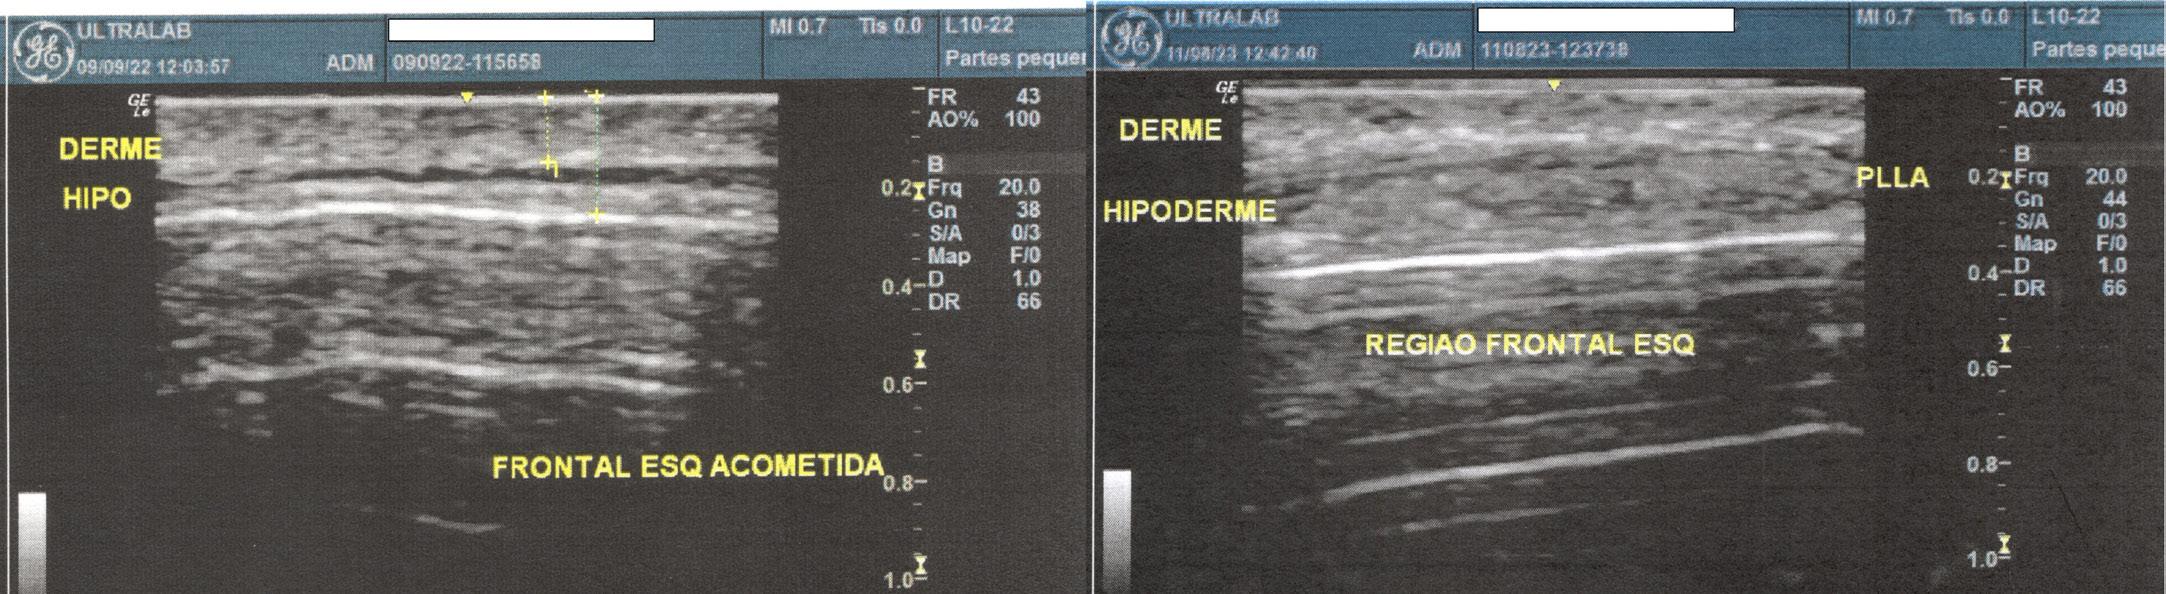

Tratamento da síndrome de Parry-Romberg e da esclerodermia linear em golpe de sabre, com aplicação do ácido

76 poli-L-láctico (PLLA): avaliação da resposta clínica e ultrassonográfica de alta resolução

Renato Roberto Liberato Rostey, Cristiane Ferreira Rallo de Almeida, Danilo Olavarria D’Aquino, Caio Leal Carvalho